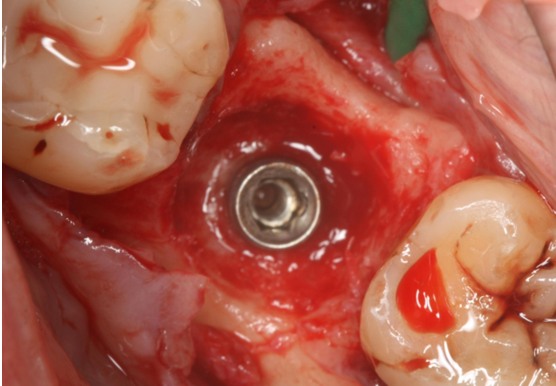

Τοποθέτηση εμφυτεύματος στην πρόσθια (αισθητική) ζώνη. Ασθενής ετών 30 προσήλθε στο ιατρείο παραπονούμενη για πόνο, οίδημα και πυορροή στον κεντρικό τομέα άνω δεξιά.

Το δόντι είχε κακή πρόγνωση (κάταγμα ρίζας) και για το λόγο αυτό έγινε εξαγωγή και ταυτόχρονα δημιουργία νέου οστού με τοποθέτηση μοσχεύματος και μεμβράνης (οστική ανάπλαση). Μεθύστερα, τοποθετήθηκε εμφύτευμα και η επούλωση κρίθηκε απολύτως επιτυχής.

ΕΠΟΥΛΩΣΗ ΜΕΤΑ ΤΗΝ ΑΝΑΠΛΑΣΗ